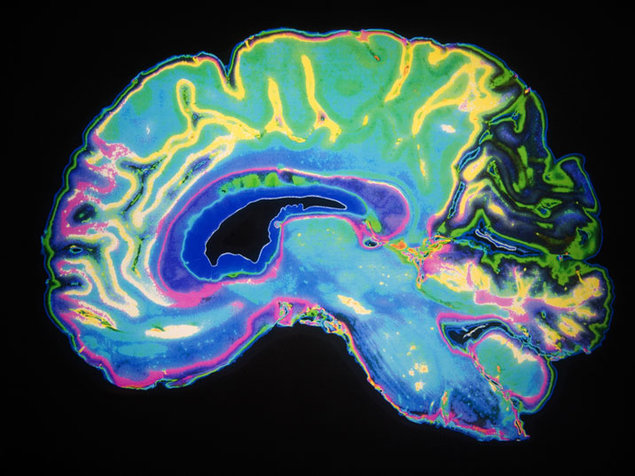

בשנים האחרונות פורסמו מאמרים רבים ובהם שלל מחקרים העוסקים בשאלה :”כיצד משפיעה עלינו בני האדם האזנה למוסיקה”? התחום נבדק באופן מעמיק ומגוון ובדק השפעות פיסיות/רפואיות/בריאותיות וכמו כן השפעות נפשיות/פסיכולוגיות/אישיות . במסגרת העבודה על התלקיט התבקשו התלמידים ללמוד את הנושא ואת המחקרים, ולחפש מידע שיעזור להם להבין את העמדות של החוקרים.בספר זה אתן לכם לטעום מן הנושא ואקווה שגם אתם, כמו התלמידים, תהיו מרותקים ותמצאו את החיבור .האישי והפרטי שלכם למוסיקה